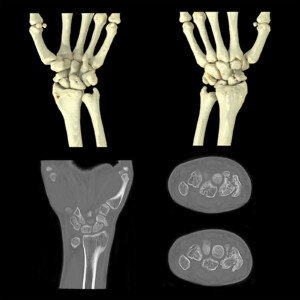

Χρησιμοποιείται για την απεικόνιση αστικών αλλοιώσεων, κηλών μεσοσπονδυλίων δίσκων, καταγμάτων κυρίως σε ασθενείς που δεν μπορούν να υποβληθούν σε μαγνητική τομογραφία μυοσκελετικού συστήματος.